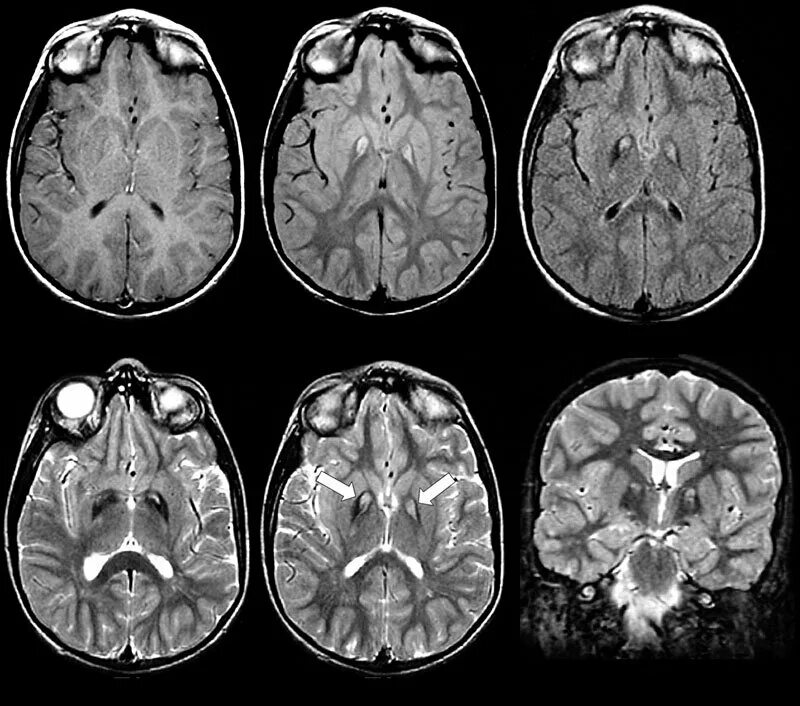

Что можно увидеть на мрт